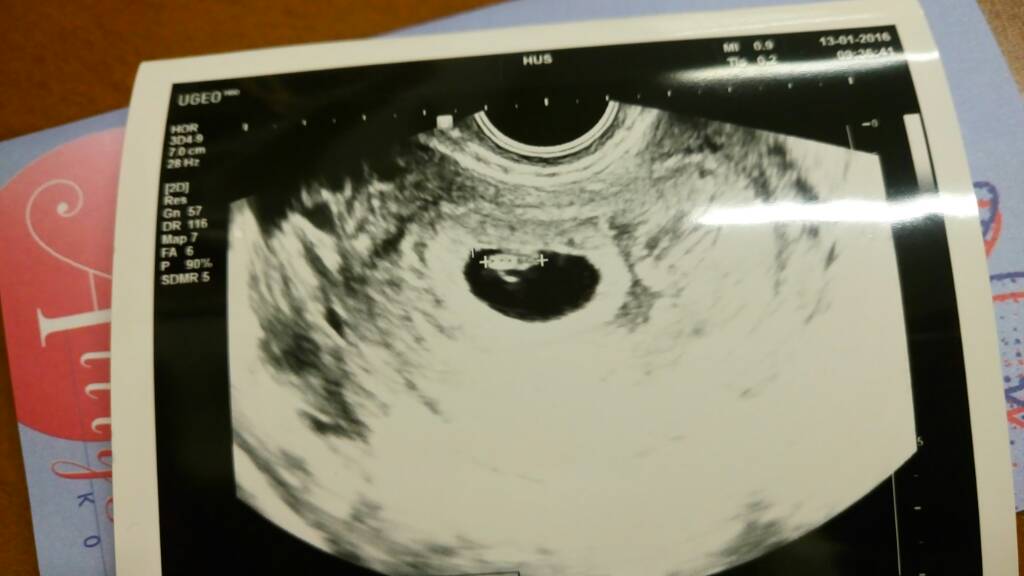

ultra

Tänään oli eka neuvola, ja ultra vasta 29.1., joka on siis ensimmäinen ultra (np-ultra). Tosi moni näyttää käyneen varhasessa vaiheessa ultrassa, itelläkin on käyny mielessä mennä yksityiselle, mutta ei ole tullut mentyä kun on sen verran kallista yksityisellä. Välillä on semmonen epäilyttävä olo että onko siellä mahassa mitään, vaikka testi oli positiivinen ja kaikki raskausoireet, mutta kun ei ole vielä nähnyt eikä kuullut sieltä mahasta "mitään".. Kai sitä pitää vaan jaksaa sinne kuun loppuun odotella.

Onko muilla ollut alavatsan kipuja / nippailuja alkuraskauden ultran jälkeen? Siis samana päivänä.

Onko muilla ollut alavatsan kipuja / nippailuja alkuraskauden ultran jälkeen? Siis samana päivänä.

Mäkin odotan sitä, (jo) toista alkuraskauden ultraa...perjantaina on, ja jännittää.

Pikkusen koosta ei vieläkään mitään koko-ikä-tietoja. Vain tää kumma laskurikiekko millä la laskettu, jippii :D

Ääk, pari tuntia vielä nt-ultraan! Jännittää ihan kauheesti. Olisinpa ees saanu sydänäänet kuuluviin dopplerilla, mut en oo. Istukan ääni kuuluu voimakkaasti.

On niin ikäväkin pientä, kun en oo sitä kolmeen viikkoon nähnyt.

Kerro sit miten kävi :) Tsemppiä!Ultra aikalailla tasan 3 tunnin päästä <3 JÄNNITTÄÄ

Rv 12+3. Mulla la ihan heinäkuun lopussa, joten oon hengaillut sekä täällä että heinäkuisissa :)

Merivesi onko 4D kuva?